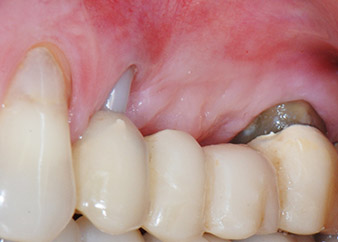

Eine 58-jährige Patientin, die auch eine gute Freundin und ärztliche Kollegin ist, beschwerte sich über Schmerzen und erhöhte Beweglichkeit ihres Brückenpfeilers 24. Es lag auch eine parodontale Entzündung vor, mit Taschentiefen von 7 mm mesiobukkal und mehr als 12 mm distal und einer Furkationsbeteiligung dritten Grades. Darüber hinaus zeigte die Röntgenaufnahme eine großflächige apikale Aufhellung am endodontisch (alio loco) vorbehandelten Zahn 24 (Abb. 1).

Einen Monat nach dem Eingriff waren sowohl die Schmerzen als auch die Entzündung an Zahn 24 minimal, die Zahnbeweglichkeit lag jedoch noch bei Miller-Klasse 2. Nach Freilegung und Reinigen des infizierten periapikalen und periradikulären Gewebes wurde das Ausmaß des Knochendefizits deutlich (Abb. 2 und 3).

An der bukkalen Wurzel fehlte der gesamte vestibuläre und distale Knochen. Das Attachment beschränkte sich weitgehend auf die palatinale Wurzel, was die anfängliche schlechte Prognose unterstreicht. Auch Zahn 27 wies ein verringertes horizontales Attachment (vgl. Abb. 12) und eine kleine apikale Aufhellung (Abb. 1) auf, allerdings ohne klinische Symptome.